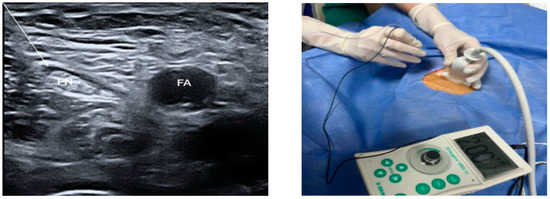

2. Materials and Methods